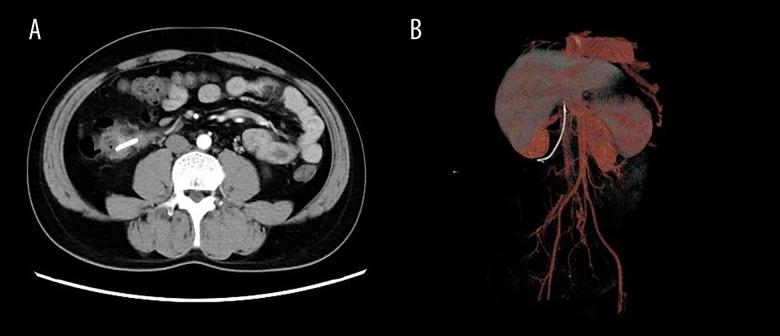

BACKGROUND Endoscopic biliary stent implantation is a recognized and effective method for the treatment of benign and malignant diseases of the bile duct and pancreas, ensuring smooth bile drainage. Currently, stent migration is considered a long-term and complex process, and in most cases, stents are removed through endoscopy or expelled from the body through the intestinal cavity. In rare cases, stents lead to formation of duodenocolic fistulas. CASE REPORT We report a case of duodenal colon fistula caused by a biliary stent penetrating the duodenum and entering the ascending colon. We removed the stent through endoscopy and clamped the fistulas of the colon and duodenum separately with titanium clips. Due to the presence of large common bile duct stones, nasobiliary drainage was performed again. Later, laparoscopic choledocholithotomy was performed, and the patient was discharged after rehabilitation. CONCLUSIONS ERCP endoscopy must consider the possibility of stent displacement in patients with biliary stents. In the case of CBD biliary stent dislocation in the patient, continuous abdominal plain films and physical examinations are required until spontaneous discharge is confirmed. In addition, for patients with benign bile duct stenosis undergoing biliary drainage, doctors should urge them to return to the hospital on time to remove the stent. For patients with postoperative abdominal pain or peritonitis symptoms, abdominal CT scan confirmation is required and early intervention should be considered.

病例报告 我们报告了一例胆管支架穿透十二指肠并进入升结肠导致的十二指肠结肠瘘病例。我们通过内镜取出了支架,并分别使用钛夹夹闭结肠和十二指肠的瘘口。由于存在大量胆总管结石,再次进行了鼻胆管引流。随后,进行了腹腔镜胆总管切开取石术,患者康复后出院。